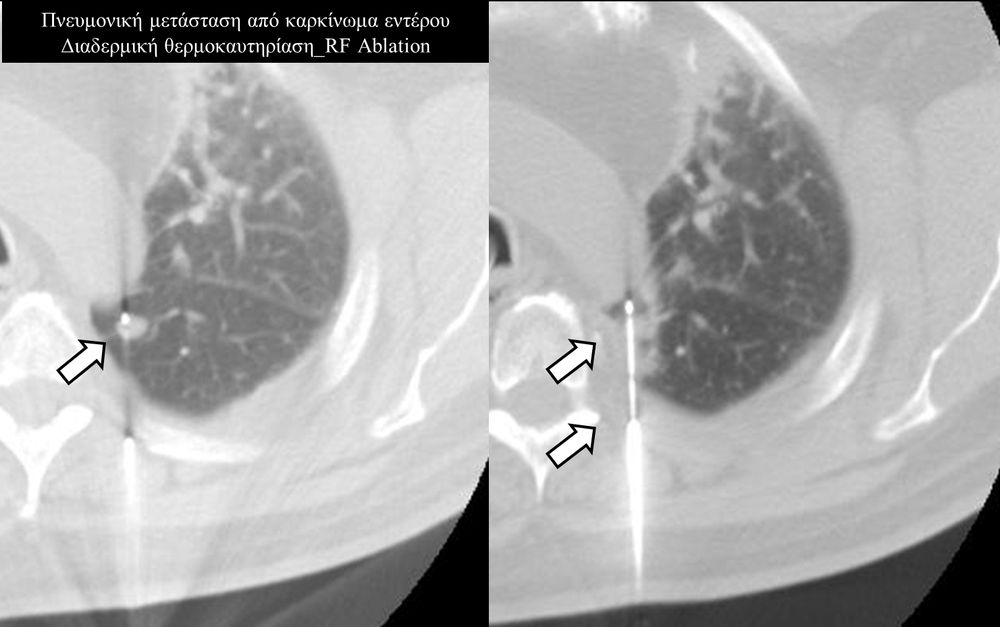

Πρόκειται για την πιο σύγχρονη τοπική θεραπεία όγκων του ήπατος, του νεφρού, του πνεύμονα, των οστών και των όγκων μαλακών μορίων. Παθοφυσιολογικά βασίζεται στην τοπική καταστροφή των καρκινικών κυττάρων με τη δημιουργία ιδιαίτερα υψηλών θερμοκρασιών εντός του όγκου. Αυτό επιτυγχάνεται με τοποθέτηση ειδικών ηλεκτροδίων εντός του όγκου υπό ακτινολογική καθοδήγηση (αξονικός τομογράφος ή υπέρηχος). Τα ηλεκτρόδια αυτά παράγουν υψηλή θερμοκρασία είτε με τη βοήθεια ραδιοσυχνοτήτων (RFablation), είτε με τη βοήθεια μικροκυμάτων (MWablation) και προκαλούν πηκτική νέκρωση των καρκινικών κυττάρων χωρίς να επηρεάζουν τα φυσιολογικά κύτταρα.Το αποτέλεσμα είναι μόνιμο.